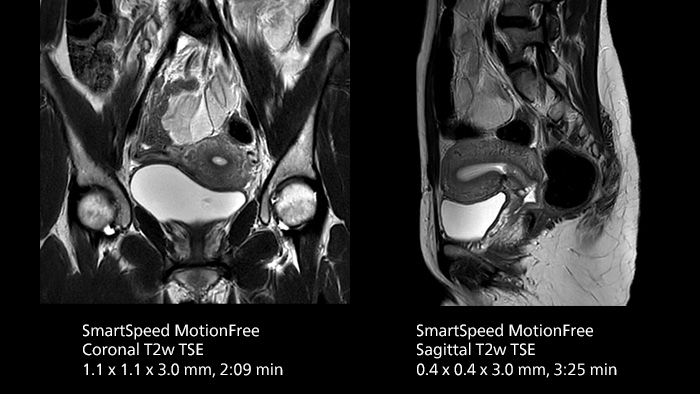

- Motion robustness and high-resolution uterus protocol

- Motion robustness and high-resolution uterus protocol